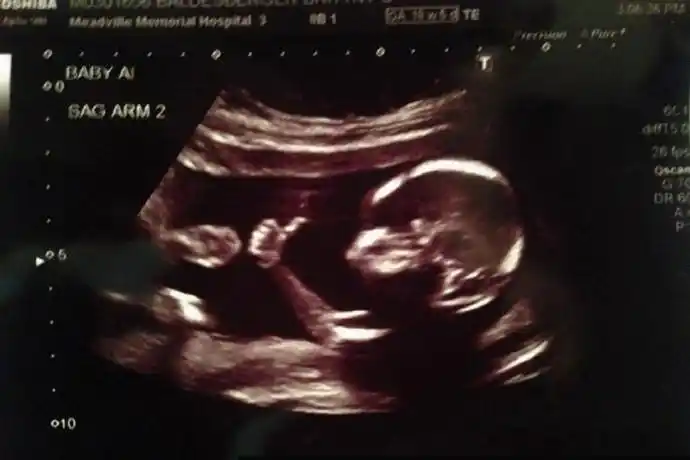

怀孕18周胎儿彩超图

做b超检查,才18周大的小胎儿在子宫里点了个赞